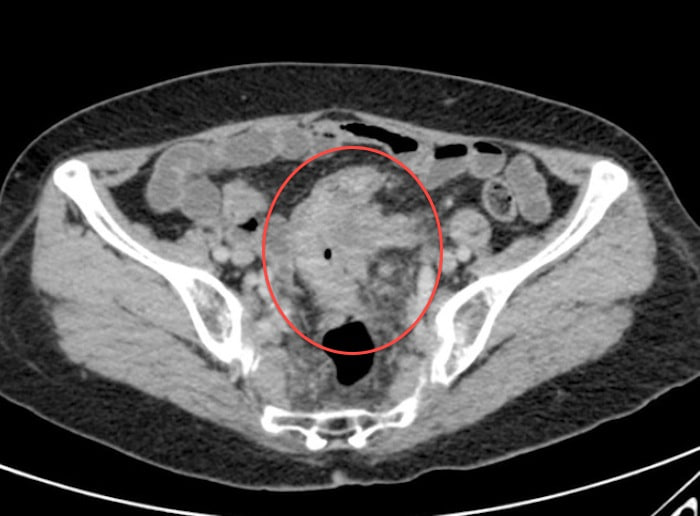

Рак кишечника на мрт 115 фото